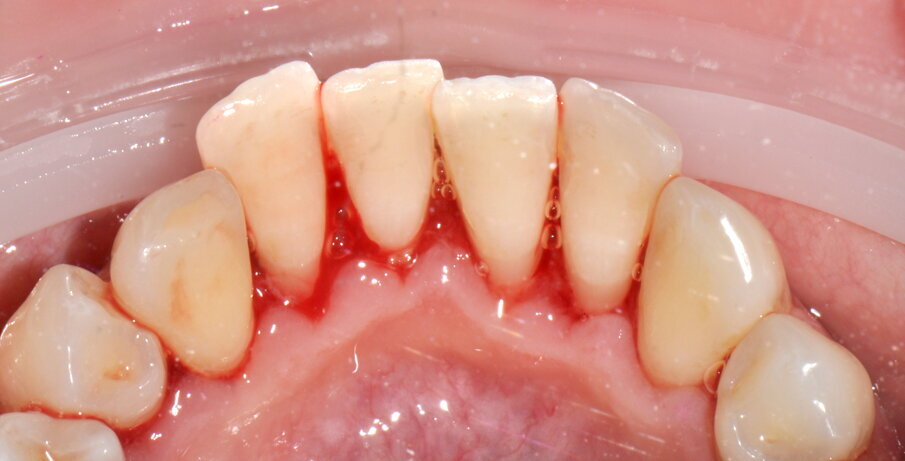

- Debridement meccanico con strumentazione piezoelettrica No-Pain® che rispetta i tessuti dentali grazie ai movimenti lineari e al controllo automatico della potenza emessa in base alla resistenza incontrata, con livello di potenza 50% e di irrigazione 100%, solo nelle zone in cui il tartaro è presente fino a sua completa rimozione (3a-4f);

Figg. 2a-2c - Foto scattate dopo l’utilizzo del manipolo sopra-gengivale, nelle aree vestibolare (2a), palatale (2b) e linguale (2c), senza la detartrasi con strumento piezoelettrico.